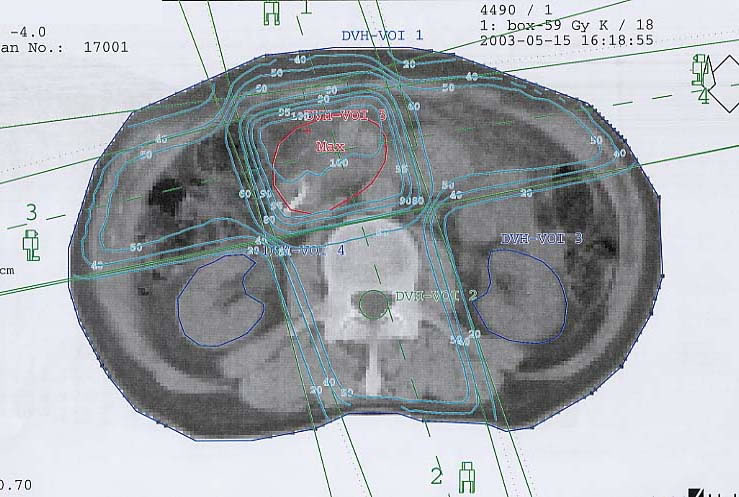

Tumore der Bauchspeicheldrüse (Pankreas): Bestrahlungsplan

Bestrahlungspläne